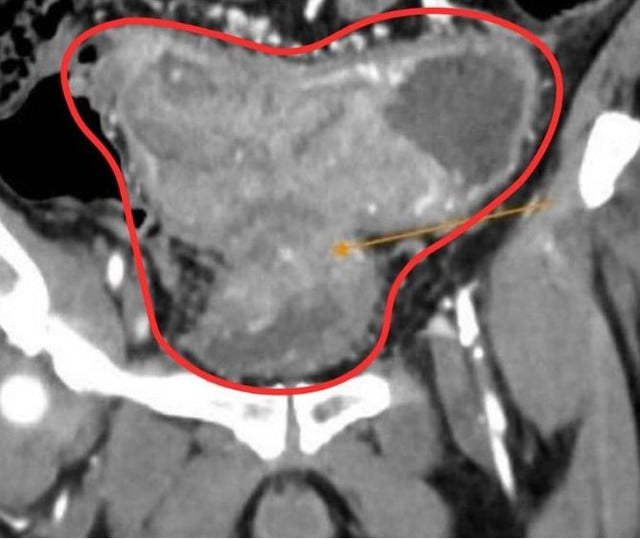

ครอบครัวของนายเอ็มได้นำตัวเขากลับไปที่โรงพยาบาลทัมอันห์ในนครโฮจิมินห์เพื่อตรวจร่างกาย ผลการสแกนซีทีสแกนช่องท้องเผยให้เห็นเนื้องอกร้ายที่ทำให้ช่องลำไส้แคบลงอย่างสมบูรณ์ นำไปสู่การอุดตันของอุจจาระและการบุกรุก ส่งผลให้ผนังกระเพาะปัสสาวะหนาขึ้น ที่น่าสังเกตคือ ตับมีรอยโรคสองแห่งเนื่องจากมะเร็งลำไส้ใหญ่ที่แพร่กระจาย

เนื้องอกร้ายสามารถทำให้ช่องลำไส้แคบลงจนหมด ทำให้เกิดอุจจาระอุดตันและขยายตัว รวมถึงการบุกรุกทำให้ผนังกระเพาะปัสสาวะหนาขึ้น